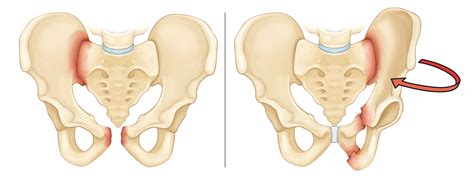

Understanding the Pelvic Anatomy

The pelvis is a ring-shaped structure composed of several bones, including the ilium, ischium, and pubis. The pubic ramus is a part of the pubis bone and plays a significant role in supporting the pelvic ring. A fracture in this area can disrupt the stability of the pelvis and affect mobility and daily activities.